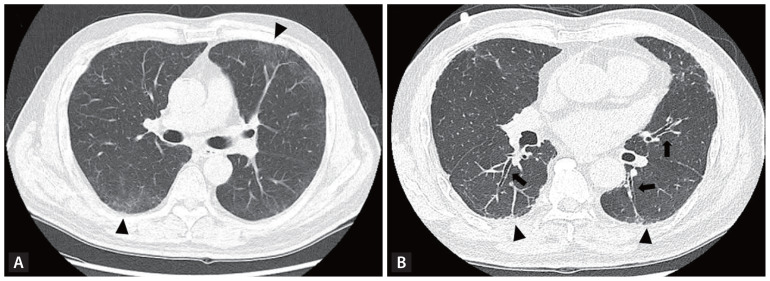

Interstitial lung abnormalities (ILAs) are early indicators of interstitial lung disease, often identified incidentally via computed tomography of the chest. This review explores the diagnostic criteria for ILAs as outlined by the Fleischner Society, highlights associated risk factors, examines their impact on patient outcomes, and discusses management strategies. The prevalence of ILAs varies significantly, ranging from 3% to 17% across populations. Key risk factors include advanced age, smoking status, and underlying genetic predispositions. Recent advancements in imaging analysis, particularly through automated quantitative systems, have enhanced the accuracy of ILA detection. Although often subtle in presentation, ILAs hold clinical significance due to their associations with impaired lung function, progressive fibrosis, and increased mortality. Therefore, monitoring and management plans should be individualized to the risk profile of patients. Further studies are needed to refine ILA diagnostic criteria, enhance our understanding of their clinical implications, and establish optimal timing for therapeutic interventions.